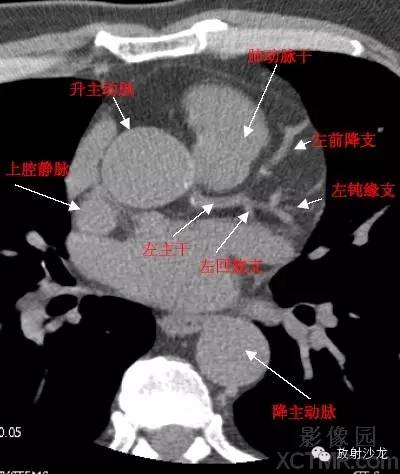

A.Aorta-Ascending Aorta升主动脉

D. Aorta-Descending Aorta降主动脉

SVC –Superior Vena Cava上腔静脉

PA -Pulmonary Artery肺动脉

LMA -Left Main Artery冠状动脉左主干

LAD -Left Anterior Descending Artery左前降支

LCX -Left Circumflex Artery左回旋支

LMB -Left Obtuse Marginal Branch 左边缘支(钝缘支)